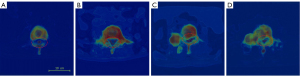

In order to solve the issue of the few-shot dataset, we utilized a segmentation network to extract key features. And pre-trained the classification network on the large-scale dataset ImageNet1000, and then used TL on our dataset to obtain the optimal network parameters. The key features of the spinal cord, spine, and tumor were extracted to form corresponding weight feature matrices, which are then transformed and combined into three-channel color images. These images served as input data for the compression grading classification network. As shown in Figure 8, feature maps of different grades are used as input for the classification network to enhance classification accuracy. Among them, Figure 8A,8B represent grade 0, indicating low-risk compression with intact spinal canal and uncompressed spinal cord; Figure 8C,8D represent grade 1, indicating high-risk compression with bone tumor invading the spinal canal region.